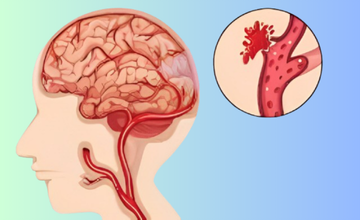

Occurs when a weakened blood vessel ruptures, causing bleeding in or around the brain, leading to pressure and tissue damage.

Bleeding inside or around the brain caused by trauma, hypertension, or aneurysms, resulting in swelling, pressure, and impaired function.